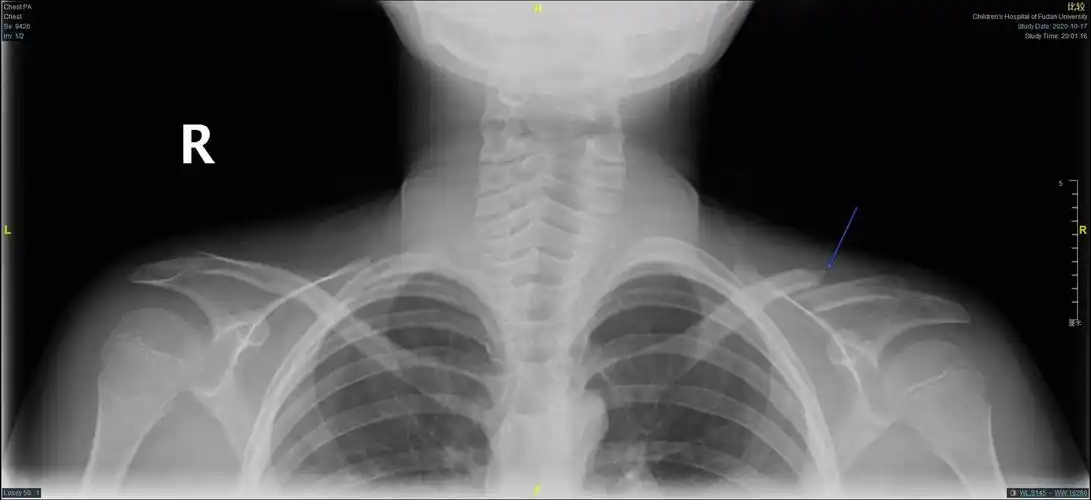

儿童锁骨骨折手术治疗(大于12岁)